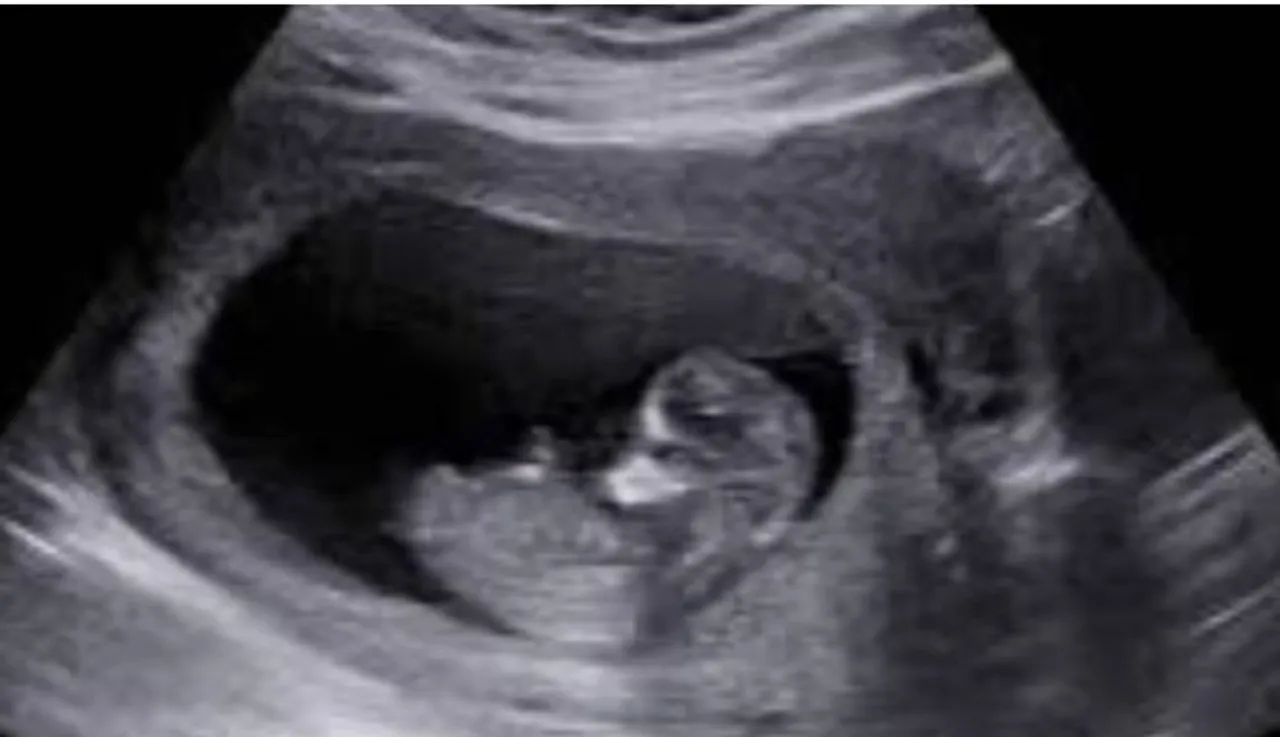

ഡോക്ടർമാരുടെ നിർദ്ദേശാനുസരണം രണ്ടു സ്വകാര്യ സ്കാനിംഗ് സെന്ററുകളിൽ നിന്നും നിരവധി തവണ സ്കാൻ ചെയ്തിട്ടും ഗർഭസ്ഥ ശിശുവിന്റെ അംഗവൈകല്യത്തെകുറിച്ച് ചികിത്സിച്ചിരുന്ന വനിതാ ഡോക്ടർമാർ തന്നെ അറിയിച്ചില്ലെന്ന് ലജനത്ത് വാർഡ് സ്വദേശിനി കമ്മീഷനെ അറിയിച്ചു.

കുഞ്ഞിന്റെ ചലനവും അംഗവൈകല്യവും അറിയാൻ കഴിയുന്ന ഒബ്സ്റ്റട്രിക് സോണോഗ്രഫി അനോമലി എന്ന സ്കാൻ എടുത്തതാണെന്നും പരാതിക്കാരി അറിയിച്ചു. എന്നിട്ടും ഡോക്ടർമാർ വിവരം പറഞ്ഞില്ല.